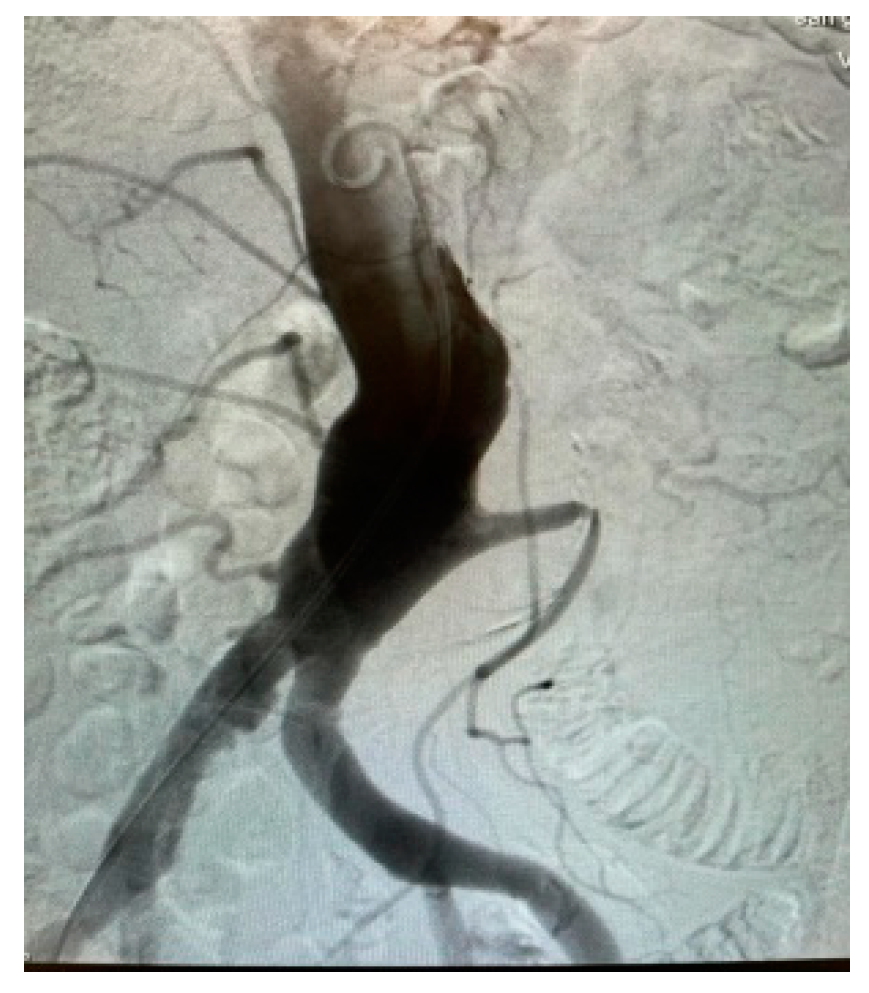

Appendix A.2. Clinical Case 2: Treatment of Endoleak Type II Inferior Mesenteric Artery